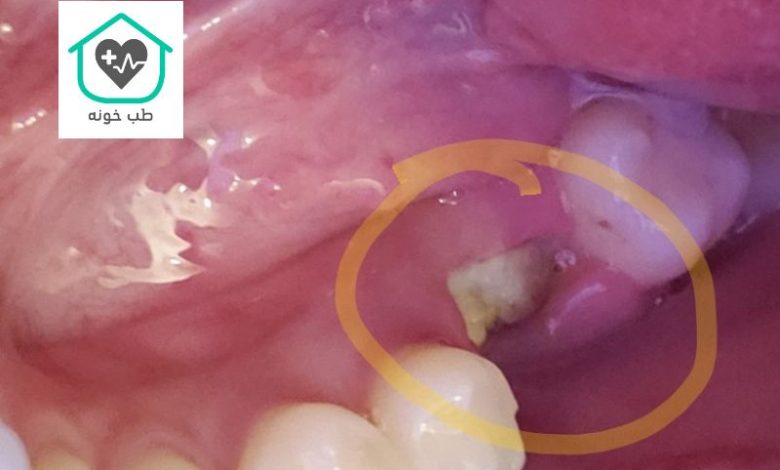

در برخی موارد نادر، پس از کشیدن دندان ممکن است تکههای کوچکی از ریشه دندان یا استخوان در حفره باقی بمانند. این بقایا که به آن “تکههای استخوانی” یا “فنوسترا” نیز گفته میشود، گاهی اوقات به صورت یک برآمدگی سفید رنگ روی لثه دیده میشوند. این حالت معمولاً با درد همراه نیست و ممکن است به مرور زمان توسط بافت لثه پوشانده شود یا به خودی خود از بین برود.

اما اگر باقیمانده بزرگ باشد یا باعث ناراحتی شود، ممکن است نیاز به برداشتن آن توسط دندانپزشک باشد. این وضعیت معمولاً در فرآیندهای پیچیدهتر مانند جراحی و کشیدن دندان عقل رخ میدهد. اگر یک برآمدگی سفید و سفت را روی لثه خود مشاهده کردید، بهتر است برای بررسی دقیق به دندانپزشک مراجعه کنید تا از عدم وجود مشکل مطمئن شوید.